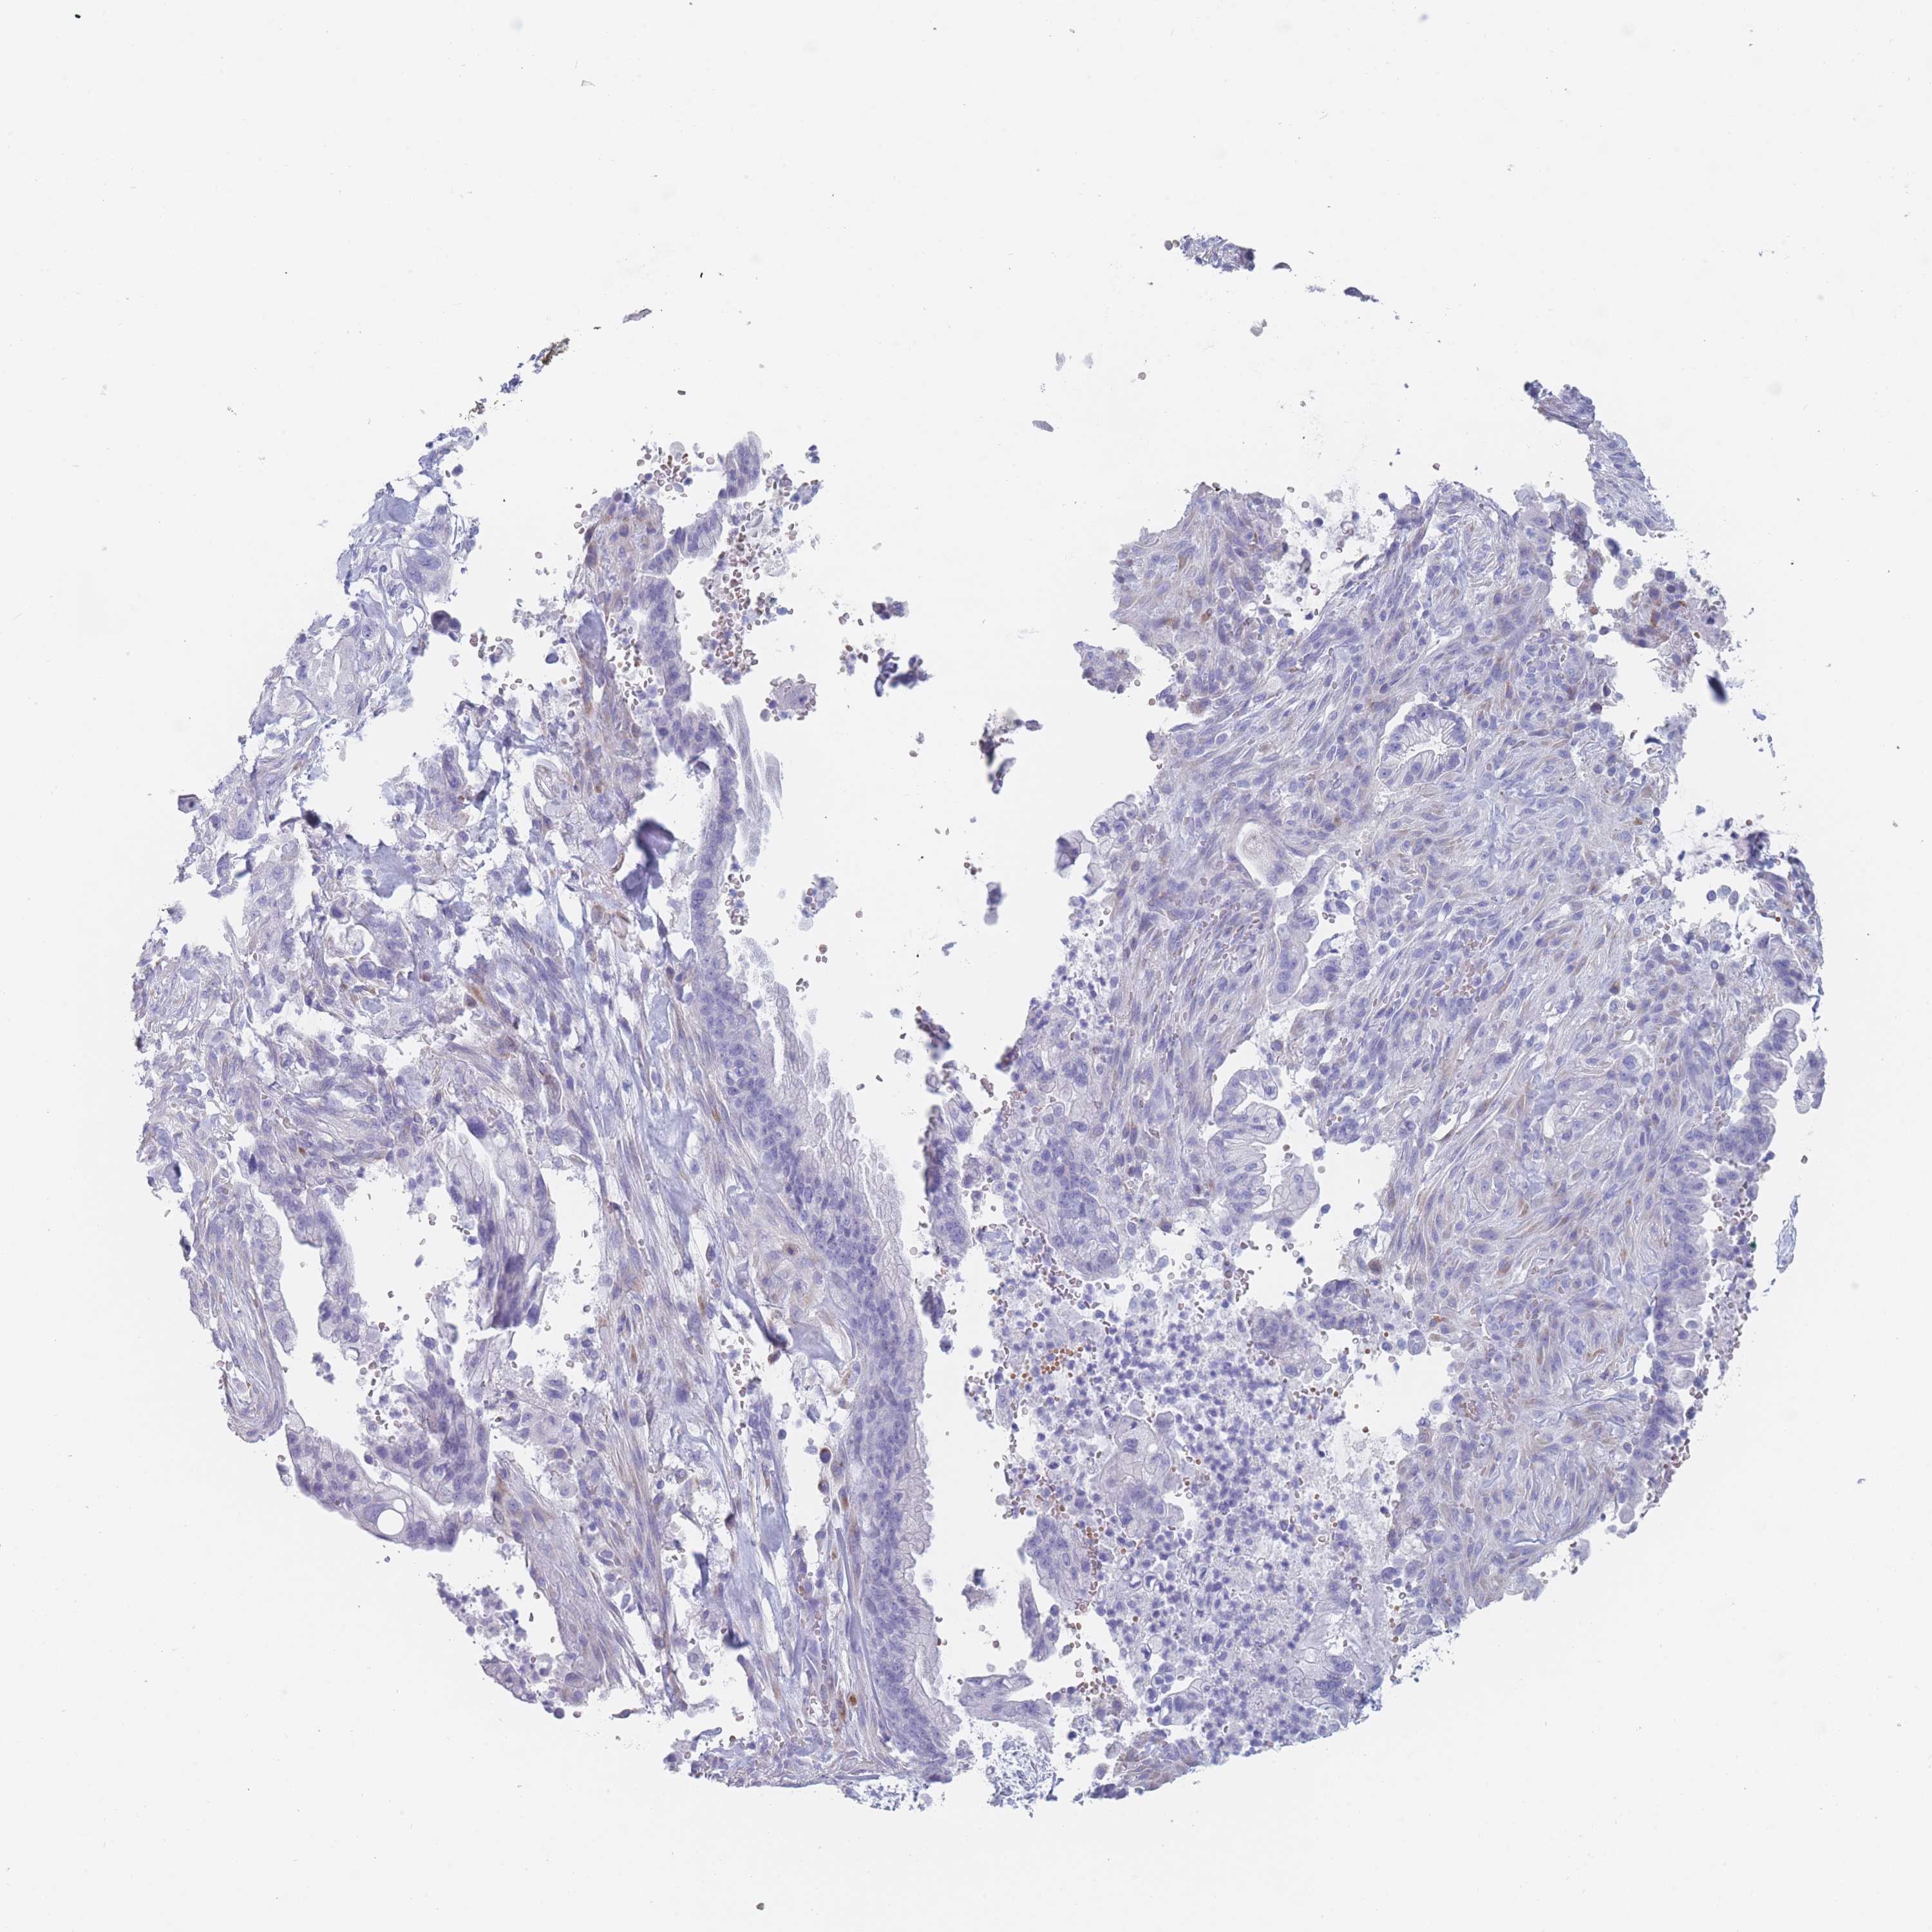

PANCREATIC CANCER - Protein expressioni

A mouse-over function shows sample information and annotation data. Click on an image to view it in a full screen mode. Samples can be filtered based on level of antibody staining by selecting one or several of the following categories: high, medium, low and not detected. The assay and annotation is described here.

Note that samples used for immunohistochemistry by the Human Protein Atlas do not correspond to samples in the TCGA dataset.

Antibody stainingi

Antibody staining in the annotated cell types in the current human tissue is reported as not detected, low, medium, or high, based on conventional immunohistochemistry profiling in selected tissues. This score is based on the combination of the staining intensity and fraction of stained cells.

Each image is clickable and will lead to virtual microscopy that enables deeper exploration of all samples and also displays staining intensity scores, fraction scores and subcellular localization as well as patient and tissue information for each sample.

Antibody HPA046711

Staining

High

Medium

Low

Not detected

Intensity

Strong

Moderate

Weak

Negative

Quantity

>75%

75%-25%

<25%

None

Location

Nuclear

Cytoplasmic/membranous

Cytoplasmic/membranous,nuclear

Adenocarcinoma, NOS